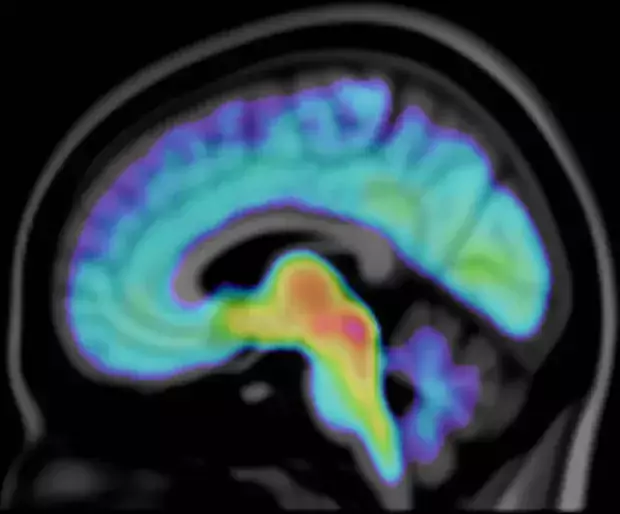

A Core Facility for molecular imaging of the brain using Positron Emission Tomography (PET).

Positron Emission Tomography (PET) is an unsurpassed method for imaging biochemical and physiological processes in vivo.